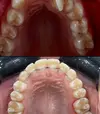

Dental Crowding